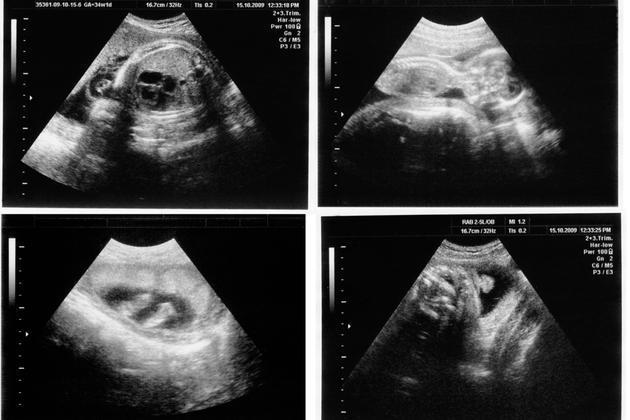

Na první pohled by se mohlo zdát, že zase o tolik nejde. Odkaz na těhotenském testu se přece nerovná zákazu interrupcí. Jenže podobná opatření, jejichž konečný cíl – tedy míchat se ženám do toho, zda smějí ukončit svoje těhotenství – je nasnadě, představují v oblasti ženských reprodukčních práv velmi tenký led. Například maďarské ženy musejí poslouchat tlukot srdce embrya nebo plodu, zatímco Němkám ztěžují potratové podmínky povinné konzultace s poradenskou službou. Všechna tato nařízení, která kolem zákazu jen opatrně krouží, mají nakonec za cíl jediné: interrupce znesnadnit, znechutit, a jednoho dne možná i zcela vymýtit. Není důvod, aby na tuto dráhu nastupovalo také Česko, kde podle průzkumu CVVM z dubna a května 2023 souhlasí s právem na interrupci čtyři pětiny lidí. O svém těle ať se rozhodne každý sám za sebe. Nepotřebujeme, abyste nás spasili.